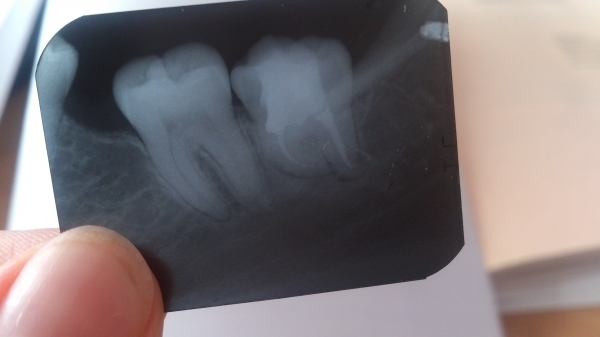

Пролечены и запломбированы каналы в правой нижней восьмерке, сверху стоит временная пломба. В течение 4-х дней после пломбирования каналов беспокоит сильная боль при накусывании. Реакции на холодное, горячее нет, чищу зубы нормально. Но вот жевать на этот зуб, смыкать челюсти не получается — очень больно.

Подскажите, можно ли это считать нормой? Снимок после пломбировки каналов прилагаю.

Во-первых, это далеко не норма, и врач поставил неправильный диагноз. У Вас хроническое воспаление (периодонтит), а лечили Вас от пульпита. И вообще, по всем показаниям данный зуб необходимо удалить.